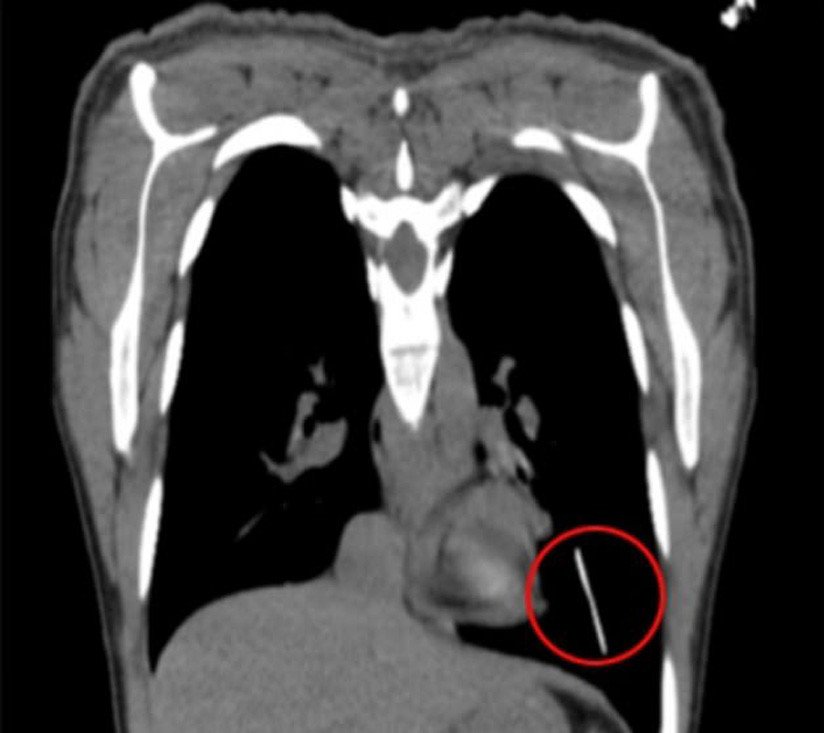

Para poder localizarlo le realizaron un estudio con ultrasonido que detalló que el Implanon NXT se había desplazado y estaba en el surco mamario izquierdo o en la pared costal lateral. Una radiografía fue lo que finalmente determinó que, en realidad, se hallaba en el lóbulo inferior del pulmón izquierdo.

Se programó entonces una cirugía toracoscópica asistida por video, sin resección pulmonar, con la que el implante pudo ser retirado. En las consultas siguientes, la mujer no presentó ninguna dificultad.